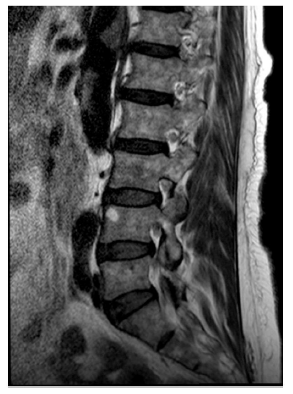

Paciente femenina, de 70 años de edad, con antecedente de infección por el virus de la hepatitis B, cirrosis hepática, hipertensión, hipotiroidismo y extabaquista, con enfermedad renal crónica en estadio 5, terapia de reemplazo renal con diálisis peritoneal, y adicionalmente falla cardíaca con función sistólica preservada. Había consultado previamente por dolor lumbar intenso, discapacitante, en cuyo estudio habían solicitado de manera ambulatoria radiografía de columna lumbosacra para cuya preparación recibió laxante osmótico con posterior cuadro de deshidratación secundario a enfermedad diarréica aguda de alto gasto, con intolerancia a la vía oral, razón por la cual consultó al servicio de urgencias. Presentó episodio de hipotensión y lipotimia, y durante su recuperación refirió disminución de la fuerza muscular en las extremidades inferiores documentando paraplejia arrefléxica en el examen físico. Inicialmente se sospechó compresión medular neoplásica o por hernia discal. Se realizó resonancia magnética nuclear contrastada de columna lumbar que demostró mielopatía, posiblemente isquémica, que comprometía la cauda equina, hemangioma en T7-T8 y abombamiento discal L3-L4 sin compromiso del canal medular (figs. 1-3). Se solicitó angiotomografía de abdomen que evidenció trombo intramural e intraluminal de la aorta abdominal con una extensión longitudinal de 7,5 cm por encima de los vasos viscerales sin disección de aorta, ateromatosis aórtica severa y aspecto irregular, posiblemente ulcerado de la misma, a nivel torácico sospechoso de aorta shaggy (fig. 4), con múltiples infartos esplénicos por tomografía (fig. 5). Ante el cuadro neurológico se sospechó ateroembolia de la arteria de Adamkiewicz; sin embargo, no fue posible visualizarla en las imágenes obtenidas (caso llevado a staff de Radiología y Neurocirugía). Se inició manejo con antiagregación dual, sin anticoagulación, con estatinas de alta potencia. Presentó dolor torácico en reposo, por lo que se realizó ecocardiografía de estrés con dobutamina que fue máxima positiva para isquemia en la pared inferior. Fue llevada a coronariografía y se documentó además enfermedad coronaria de dos vasos con oclusión total de la arteria coronaria derecha y lesión en la arteria circunfleja no susceptible de intervencionismo percutáneo. Por múltiples comorbilidades, edad avanzada y pobre red de apoyo familiar se continuó manejo conservador con antiagregación con ácido acetil salicílico, anticoagulación con warfarina y estatinas de alta potencia.

Figura 1 Resonancia magnética nuclear contrastada de columna lumbar en la que se evidenció (de izquierda a derecha) hemangioma en T7-T8, abombamiento discal L3-L4 y mielopatía, posiblemente isquémica, con compromiso de cauda equina.

Figura 2 Resonancia magnética nuclear contrastada de columna lumbar en la que se evidenció (de izquierda a derecha) hemangioma en T7-T8, abombamiento discal L3-L4 y mielopatía, posiblemente isquémica, con compromiso de cauda equina.

Figura 3 Resonancia magnética nuclear contrastada de columna lumbar en la que se evidenció (de izquierda a derecha) hemangioma en T7-T8, abombamiento discal L3-L4 y mielopatía, posiblemente isquémica, con compromiso de cauda equina.